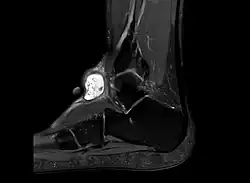

Die Diagnose eines Ganglions kann meist schon durch dessen Lokalisation oder Form gestellt werden. Die darüber liegende Haut ist verschiebbar, es besteht eine unveränderliche Verbindung zum Gelenk oder zur Sehnenscheide. Da aber auch andere Veränderungen ein ähnliches Bild bieten können, ist meist eine Sicherung der Diagnose nötig. Dies kann beispielsweise durch Nadelaspiration der Flüssigkeit, Ultraschall oder chirurgische Intervention geschehen. Im normalen Röntgenbild ist ein Ganglion nicht sichtbar. Die Röntgenaufnahme dient aber zum Ausschluss einer Knochenvorwölbung (Exostose). Besonders an der Basis des dritten Mittelhandknochens kann es auf dem Handrücken zu einer solchen Exostose kommen, die als Carpal boss mit einem Ganglion verwechselt werden kann.